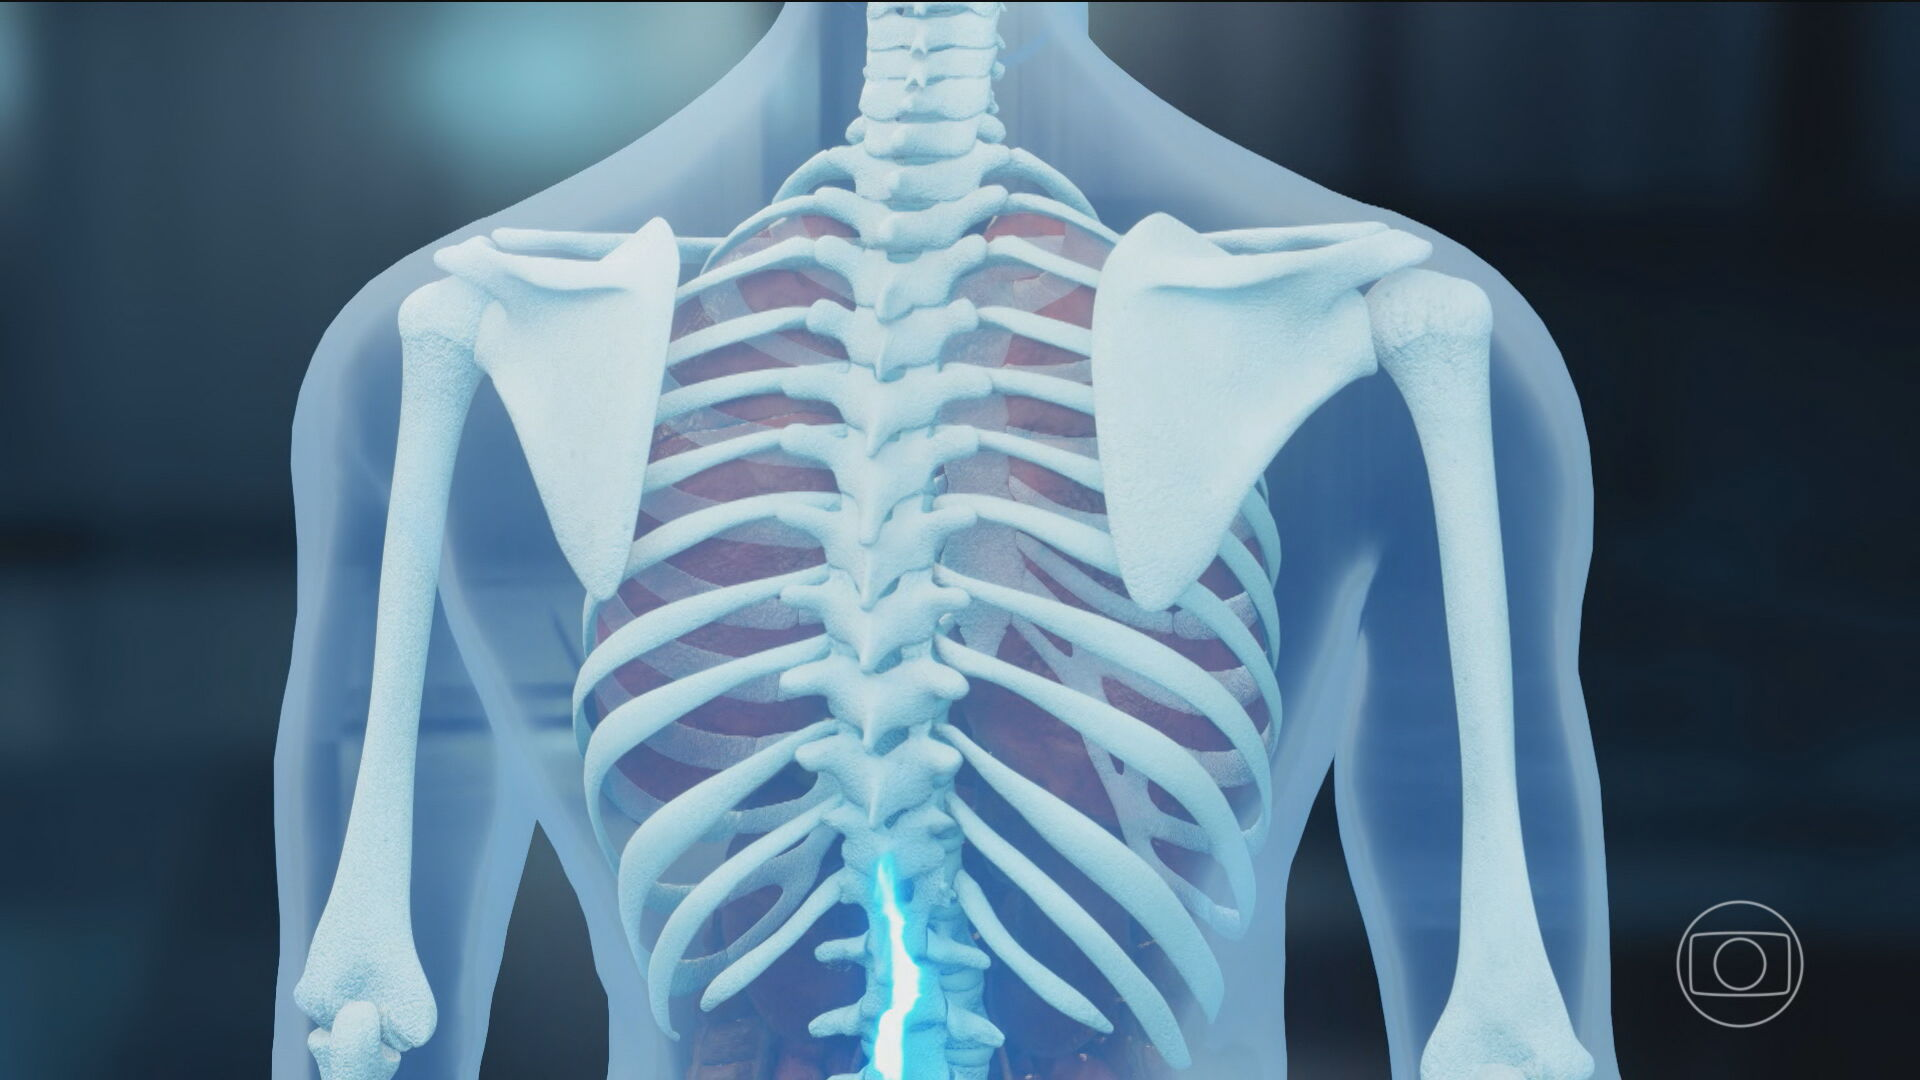

Los pacientes en lesiones en la médula han resucitado las expectativas de las médulas espinales desarrolladas a partir de la placenta humana para recuperar el movimiento del tratamiento brasileño en la etapa experimental, una condición que puede causar daño parcial o total y puede dañarse hasta hoy. La sustancia conocida como poilamineina ha sido estudiada durante más de 20 años por la Universidad Federal Río de Janeiro (UFRJ). El compuesto es una versión re -hecha de laminina laminina, que es una proteína presente en el desarrollo del feto y ayuda a conectar las neuronas. Se espera que se aplique al punto de la lesión, alienta a los nervios a crear nuevas rutas y recuperar la parte del movimiento del movimiento. Los resultados del perro publicados en las Fronteras en Ciencias Veterinarias en agosto evaluaron la polilamineína del perro paralízico, que no caminó después de la cirugía y unos pocos meses de fisioterapia. Algunos no han ido por años. Después de aplicar la sustancia directamente a la médula espinal, cuatro animales pudieron tomar medidas y mejorar la escena de la marcha. Los dos tuvieron más progreso de prudencia. Los efectos fueron durante seis meses. No se registraron efectos secundarios graves: la diarrea se informó en un solo caso sin una conexión probada con el medicamento. Además de los perros de prueba voluntarios, los pacientes brasileños experimentales también se han aplicado a grupos pequeños en el protocolo académico de polilaminina. Según los investigadores, algunos voluntarios que perdieron sus movimientos bajo la lesión recuperaron por completo parte de la movilidad, algo que se considera imposible sin intervención. Hubo algunos informes que comenzaron desde pequeños movimientos hasta extensas ganancias, como el control del tronco e incluso el apoyo. Sin embargo, el número de personas probadas sigue siendo muy pequeña, ocho voluntarios, y los científicos han notado que los resultados deben confirmarse en estudios mayores y controlados. Los científicos brasileños usan la proteína de placenta para repatriar a los perros lesionados y los movimientos humanitarios en la TV Globo, lo que le dice a la Agencia Nacional de Vigilancia de Salud de la ANVISA (ANVSA) que no hay solicitud para el uso clínico de la polilaminina. Según el análisis, el proceso es simplemente una prueba clínica regulatoria. Según la agencia, los datos presentados hasta ahora se refieren a los niveles primarios y no clínicos: este es el resultado del laboratorio y el animal. La compañía dijo en el informe: “En las reglas regulatorias, las organizaciones responsables deben completarse antes del examen humano”. El camino de los pacientes hacia la polilamineina en realidad llega al Hospital y al Sistema de Salud Unificado (SES), aún será necesario: complete los estudios proinciales para demostrar la ausencia de animales en los animales. Comience los ensayos clínicos regulatorios en humanos, comenzando con el primer paso, centrándose en la protección del grupo más pequeño. Extienda las pruebas en la Etapa 2 y 3: evaluación, dosis apropiadas y efectos adversos en la población más grande. Solicite registro sanitario: solo entonces se puede comercializar el medicamento. Este proceso generalmente lleva algunos años e implica un análisis estricto. Las expectativas y alertas asesoran un camino comprometido hacia el progreso de los animales y los primeros voluntarios. Sin embargo, no hay tratamiento disponible hasta que se cumplan todos los pasos y la funcionalidad se confirma en el tamaño más grande. Sin embargo, Polylmyin sigue una de las investigaciones más relevantes en un campo que todavía quiere una solución específica: la regeneración de la médula espinal.